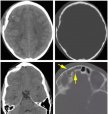

颅骨骨折是指颅骨受到猛烈作用而引起颅骨结构改变,颅骨骨折占颅脑损伤的15% ~ 20%,颅骨骨折是颅内疾病损伤的危险信号。